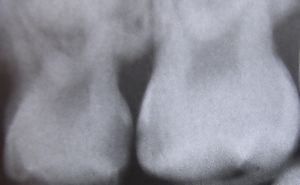

Smooth-surface caries

There are three types of smooth-surface caries. Proximal caries, also called interproximal caries, form on the smooth surfaces between adjacent teeth. Root caries form on the root surfaces of teeth. The third type of smooth-surface caries occur on any other smooth tooth surface.

التشخيص